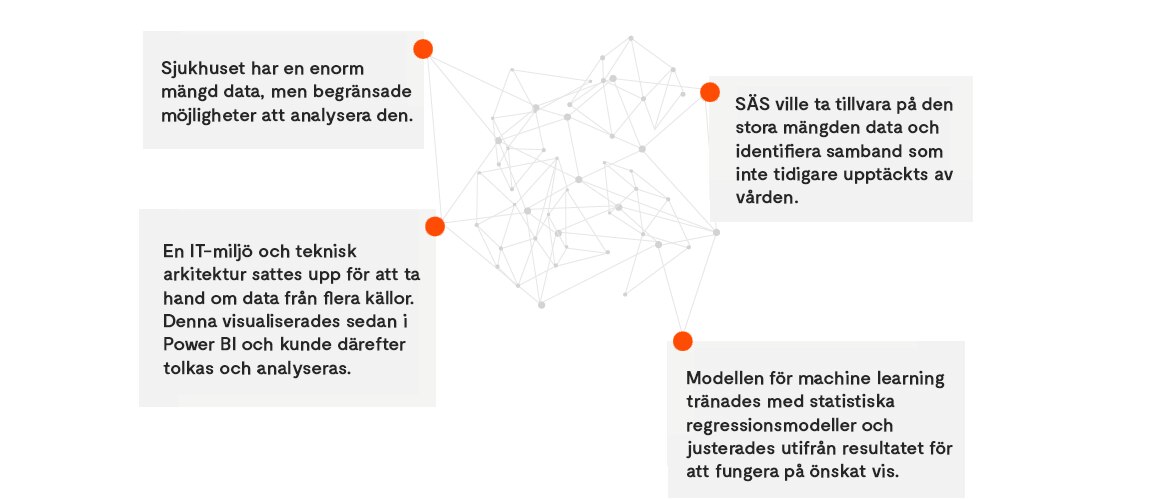

På CGI hjälpte vi Södra Älvsborgs sjukhus (SÄS) med ett projekt som fokuserade på lunginflammation, med den grundläggande frågeställningen ”Varför blir vissa patienter mer sjuka än andra?”

CGI blev ombedda att stötta med design och implementation av en IT-lösning samt kunskap om arbetsmetoder.